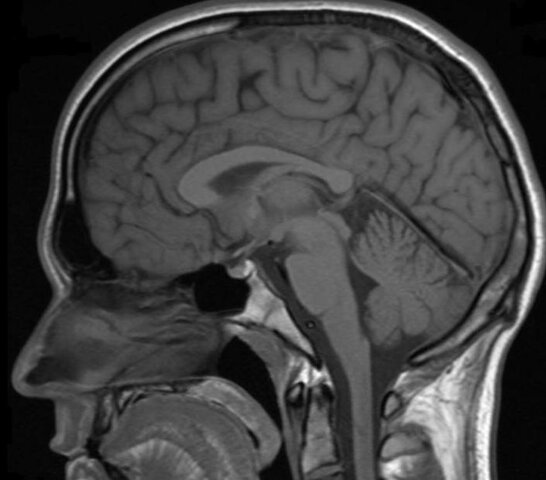

Se fortalece la investigación con el empleo de imágenes no

ya anatómicas sino funcionales, en particular la resonancia magnética funcional y la tomografía por emisión de positrones, que han permitido visualizar la actividad cerebral durante la realización de diferentes tareas cognoscitivas. Asimismo, surge un nuevo modelo en la interpretación de la organización cerebral de la cognición, el denominado “modelo funcional”. Hasta este momento se había utilizado un “modelo lesional”.